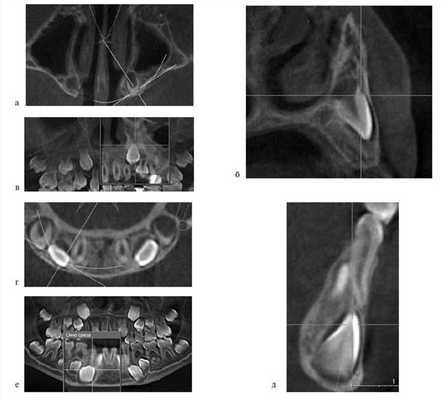

По окончании периода ретенции ортодонтическое лечение было направлено на нормализацию положения зубов, формирование оптимальной окклюзии (рис. 5, а—г).

Рис. 5. Этапы ортодонтического лечения по окончании периода ретенции. а — до костной пластики; б—г — перемещение небно расположенного бокового резца в костный регенерат; д, е — имплантат в области костного регенерата.

При адентии бокового резца в область костного регенерата вводили имплантат (см. рис. 5, д, е).